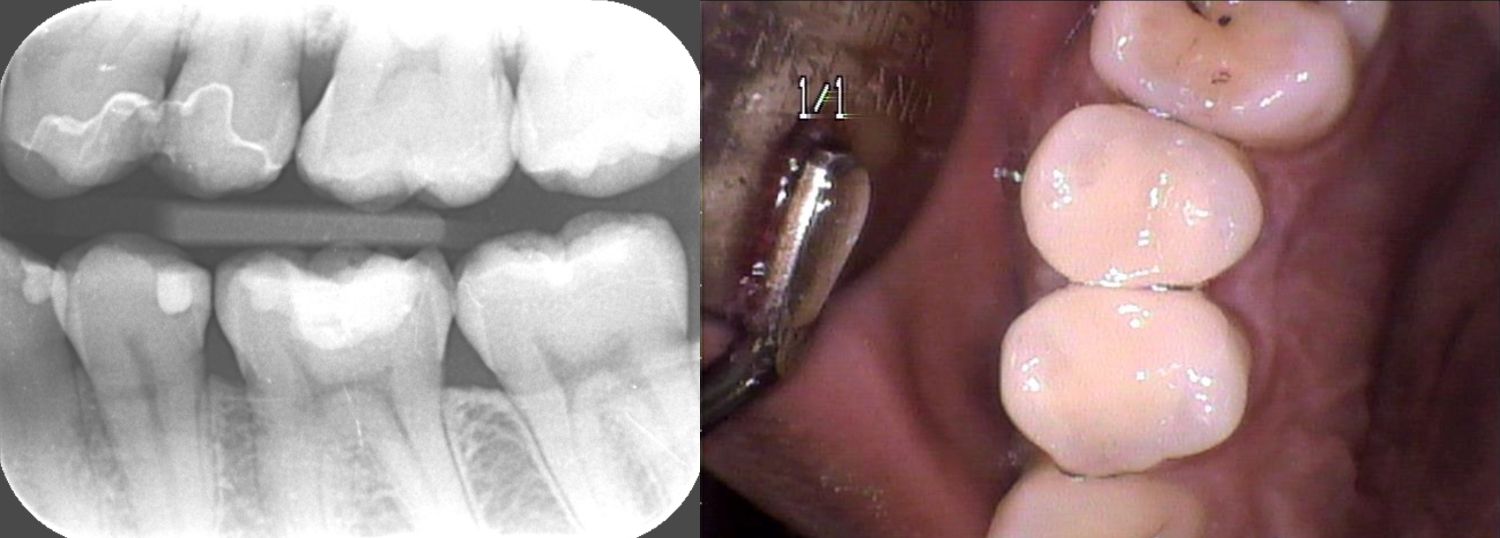

術後のレントゲン

診断 左上45う蝕

処置内容 (または主訴) セレックインレー